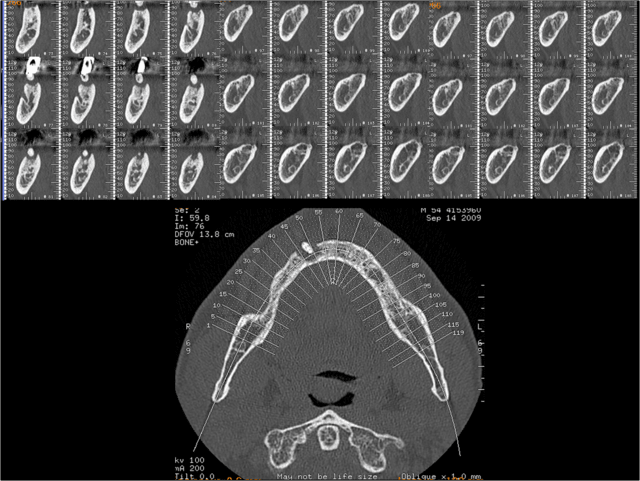

Détails en coupes.

rapport entre les implants, le N.A.I et l'artère sublinguale.

Vue d'ensemble du projet prothétique et implantaire.